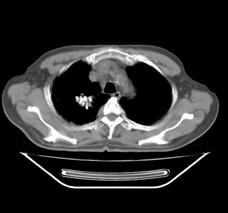

典型病例1:患者鞠xx,女,68岁,住院号:488141,因左胸痛1月余入院。2015年3月31日胸部增强CT示:左肺下叶2.5cmx2.8cm占位,左侧第三前肋骨溶骨性转移、形成厚约3cm肿块,左侧腋窝淋巴结2.1cmx4.1cm及前纵膈淋巴结转移。患者于2015年4月1日经CT引导下穿刺活检、病理证实为左肺下叶腺癌。于2015年4月5日对其采用125I放射性粒子置入治疗。治疗3个月随访,患者胸痛缓解,左肺下叶原发病灶消失,粒子聚集;左侧第三前肋骨基本恢复正常形态;前纵膈淋巴结消失,粒子聚集;左侧腋窝淋巴结缩小2/3。目前患者生活质量良好,可从事一般家务劳动。

术后三个月CT片: